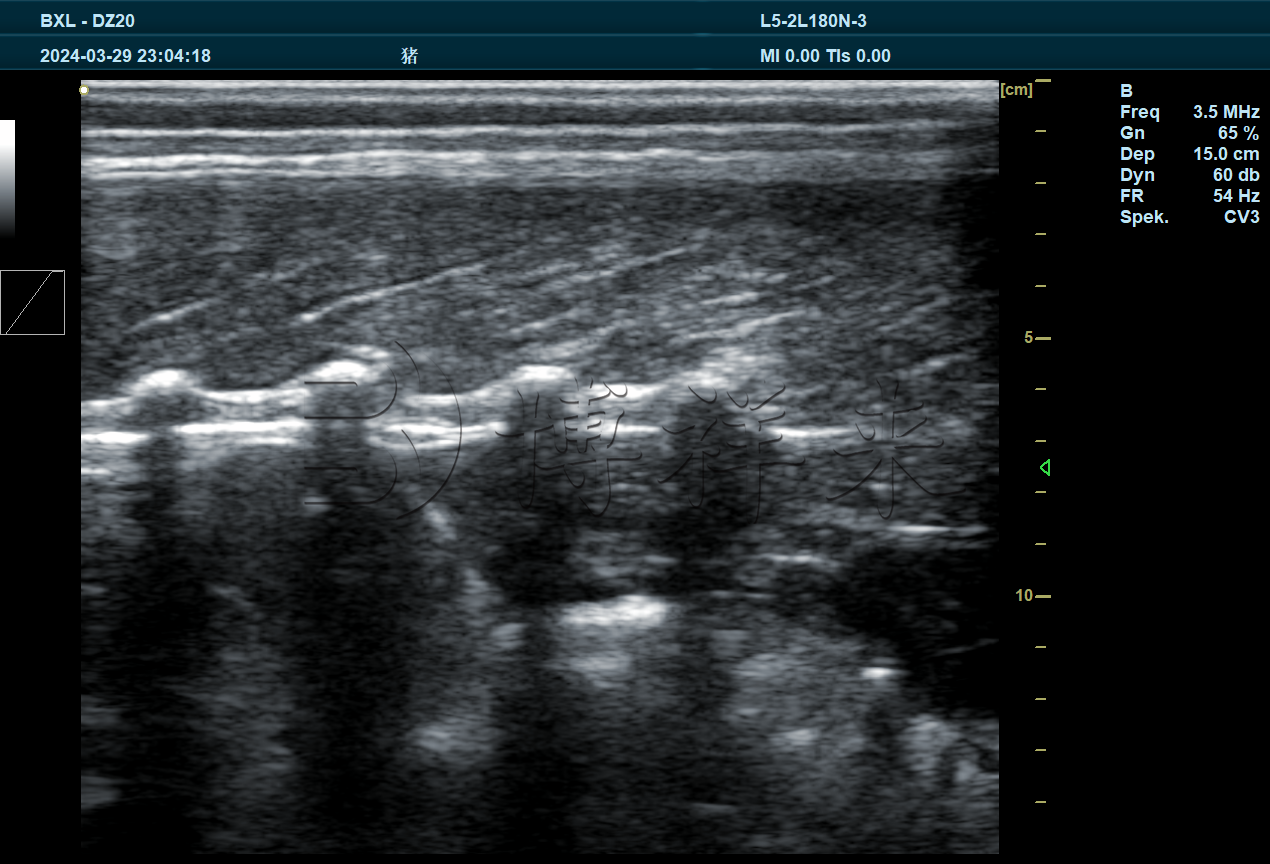

猪体形状与肉质性状的遗传评估,通常依赖于背膘厚度、眼肌面积和肌内脂肪含量这三项关键指标。BXL-DZ20测定仪采用高频线阵探头与专业图像处理软件,可以清晰显示猪只背部肌肉与脂肪层的横截面结构,实现:

背膘厚度的精准测定:通过在标准位置(第3~4肋之间)获取脂肪层图像,自动或手动标注脂肪厚度,为评估猪只瘦肉率及育种价值提供量化依据。

眼肌面积分析:通过软件描绘眼肌轮廓并计算面积,反映出猪只肌肉发育水平。

肌内脂肪含量推估:借助图像灰度与纹理特征,配合模型算法可对IMF进行估值,辅助判断肉质风味潜力。

BXL-DZ20配备高清显示屏与便携式主机,可在实验室、育种基地或现场采样点快速部署,支持实时图像冻结与存储功能,极大地方便科研数据的采集与对比分析。